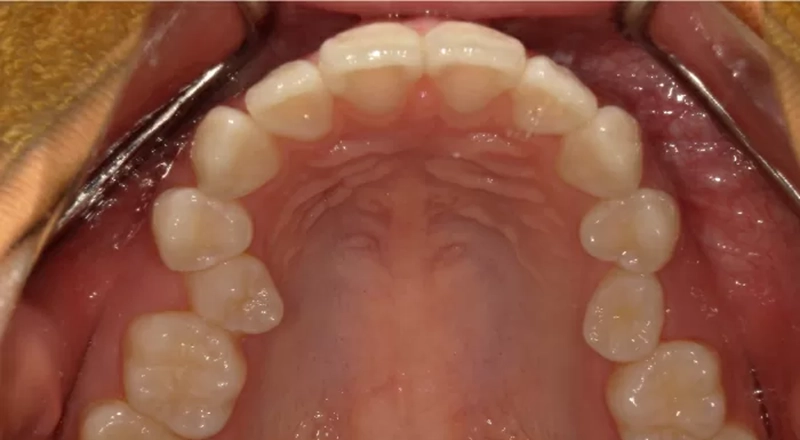

主訴:ガタガタ、治療期間:1年6ヶ月、費用:105万円、リスク:疼痛の可能性があります

主訴

歯のガタガタが気になる

治療内容

ゴールデンスマイル矯正(インビザライン+光加速装置+ホワイトニング)

治療期間

1年6ヶ月

治療費

1,050,000円

治療後のリスクについて

疼痛の可能性があります